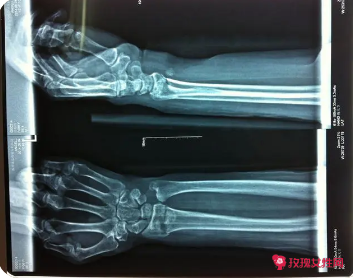

桡骨骨折的临床表现

疼痛和肿胀、 紧绷感和僵硬感、 疼痛加剧、 变形和损伤等。

桡骨骨折的临床表现1

1、 疼痛和肿胀

桡骨骨折的最常见临床表现之一是疼痛和肿胀。当人们的桡骨发生骨折时,他们会感到极度的疼痛和烧灼感。肿胀和疼痛的程度往往与骨折的程度成正比,因此更严重的骨折往往伴随着更强烈的疼痛和肿胀。

2、 紧绷感和僵硬感

桡骨骨折还会导致紧绷感和僵硬感。当人们的桡骨发生损伤时,他们的身体会产生紧绷感和僵硬感。这些感觉可能会限制人们的运动能力,并且可能会让他们感到不适和疼痛。

3、 疼痛加剧

桡骨骨折还可能导致疼痛加剧,尤其是在活动后。如果人们的桡骨骨折很严重,那么他们在活动或运动时会感到极度的疼痛。这种疼痛可能会将人们的生活质量和工作效率受到影响,因此及早治疗非常重要。

4、 变形和损伤

桡骨骨折还可能导致局部的`变形和损伤。当桡骨骨折时,人们的手臂可能会变形或者扭曲,导致肌肉和软组织的损伤。这样一来,人们的身体会变得非常脆弱,容易受到外界的攻击。